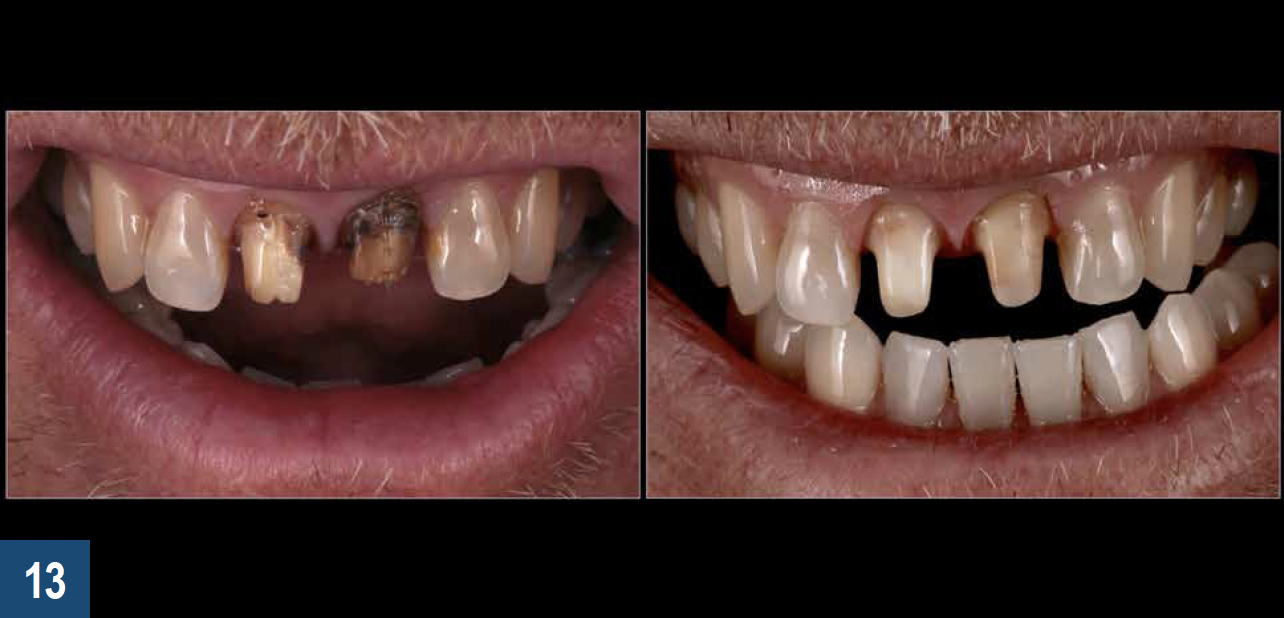

When a patient presents with previously restored nonvital anterior teeth (Figure 12), the challenge to produce a satisfactory esthetic outcome becomes a collaborative effort shared between the clinician and the dental labora-tory team. The darkened stumpf and subgingival root structure may produce an unfavorable shade to any definitive translucent ceramic restoration. In addition to its usefulness in intact nonvital teeth, the walking bleach technique with 10% carbamide peroxide is a safe and effective treatment modality for teeth with denuded enamel. Treatment to achieve the desired final shade may be completed within a single in-office application; however, the decision to discontinue internal bleaching will largely depend on the ceramist's abilities and knowledge of the materials being applied to mask the final stumpf shade of the tooth preparation (Figure 13 and Figure 14). Residual oxygen from the decomposition of 10% carbamide peroxide may remain within the dental tissues for 7 to 15 days after internal bleaching.39,40 This excess oxygen has the potential to negatively impact the bond strength of the adhesive components during the cementation of the final crowns, and it is therefore recommended that at least 2 weeks elapse before final delivery of the definitive restorations (Figure 15).41

Fig 13. Left panel: Darkened tooth stumpfs and root structure may impact the esthetics of any translucent ceramic restorations placed over them. Right panel: Internal bleaching has been shown to be an effective means of producing a more favorable substrate color that favors the achievement of an optimal esthetic final result.

Figure 13

Fig 14. The final stumpf shade should ultimately be guided by the ceramist’s knowledge of core materials (top left panel) and layering porcelain for masking the underlying tooth structure (bottom left panel).

Figure 14